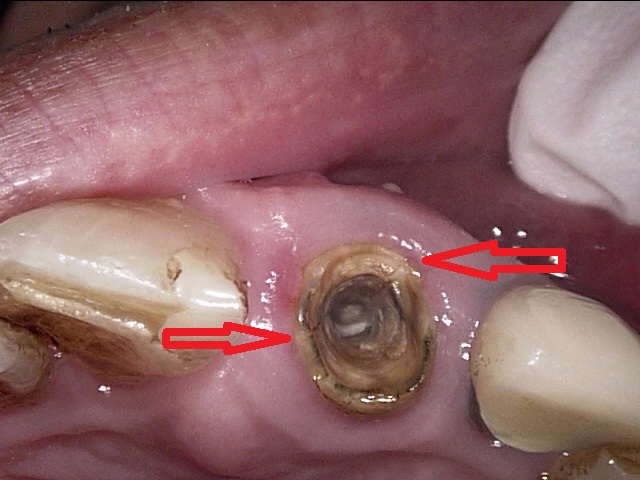

この歯を実際にお口の中で見ると、こういう風に見えます。

解説します。

赤丸の部分の歯ぐきが腫れています。矢印の部分は歯の縦に亀裂が入った様子が見られます。

この歯は大きい奥歯で、根が3本ありますが、そのうちの1本が折れており、他の2本もダメージがかなり大きかったので、無理に残しても数年持つかどうかという状態でした。

患者さんとよく話し合って、抜歯することになりました。